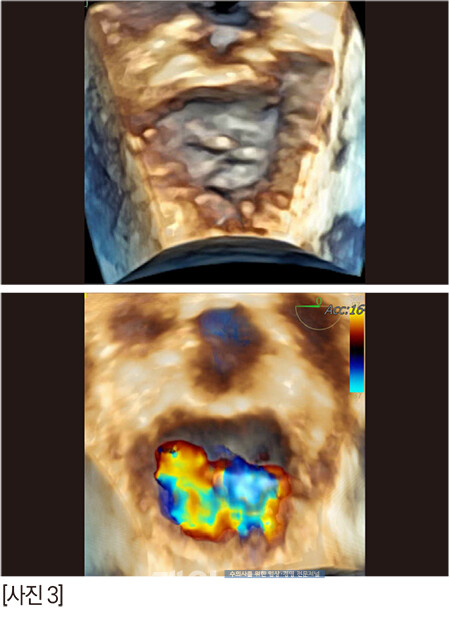

술자가 수술을 타이트하게 준비하고 각오를 하면 아이러니하게도 수술이 별일 없이 흘러간다. 마치 수혈 준비를 하고 수술을 하면 수혈할 일이 안 생긴달까[사진 7].

다행히 정답 zone에 안착했다.

수술 2시간 후의 짱아, 정말 대단하다!!!!! [사진 9] 잘 회복해서 3일차에 퇴원을 했지만 나이가 고령이어서 분명 크고 작은 문제들이 수술 2~3주 내에 지나갈 것 같았다.